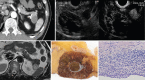

Endoscopic ultrasound (EUS) is a key modality for the evaluation of suspected pancreatic cystic neoplasms (PCNs), as the entire pancreatic gland can be demonstrated with high spatial resolution from the stomach and duodenum. Detailed information can be acquired about the internal contents of the cyst(s) [septum, capsule, mural nodules (MNs)], its relation with the main pancreatic duct (MPD), and any parenchymal changes in the underlying gland. PCNs comprise true cysts and pseudocysts. True cysts can be neoplastic or nonneoplastic. Here, we describe serous cystic neoplasm (SCN), mucinous cystic neoplasm (MCN), and intraductal papillary mucinous neoplasm (IPMN) as prototype neoplastic cysts, along with nonneoplastic lymphoepithelial cysts (LECs).